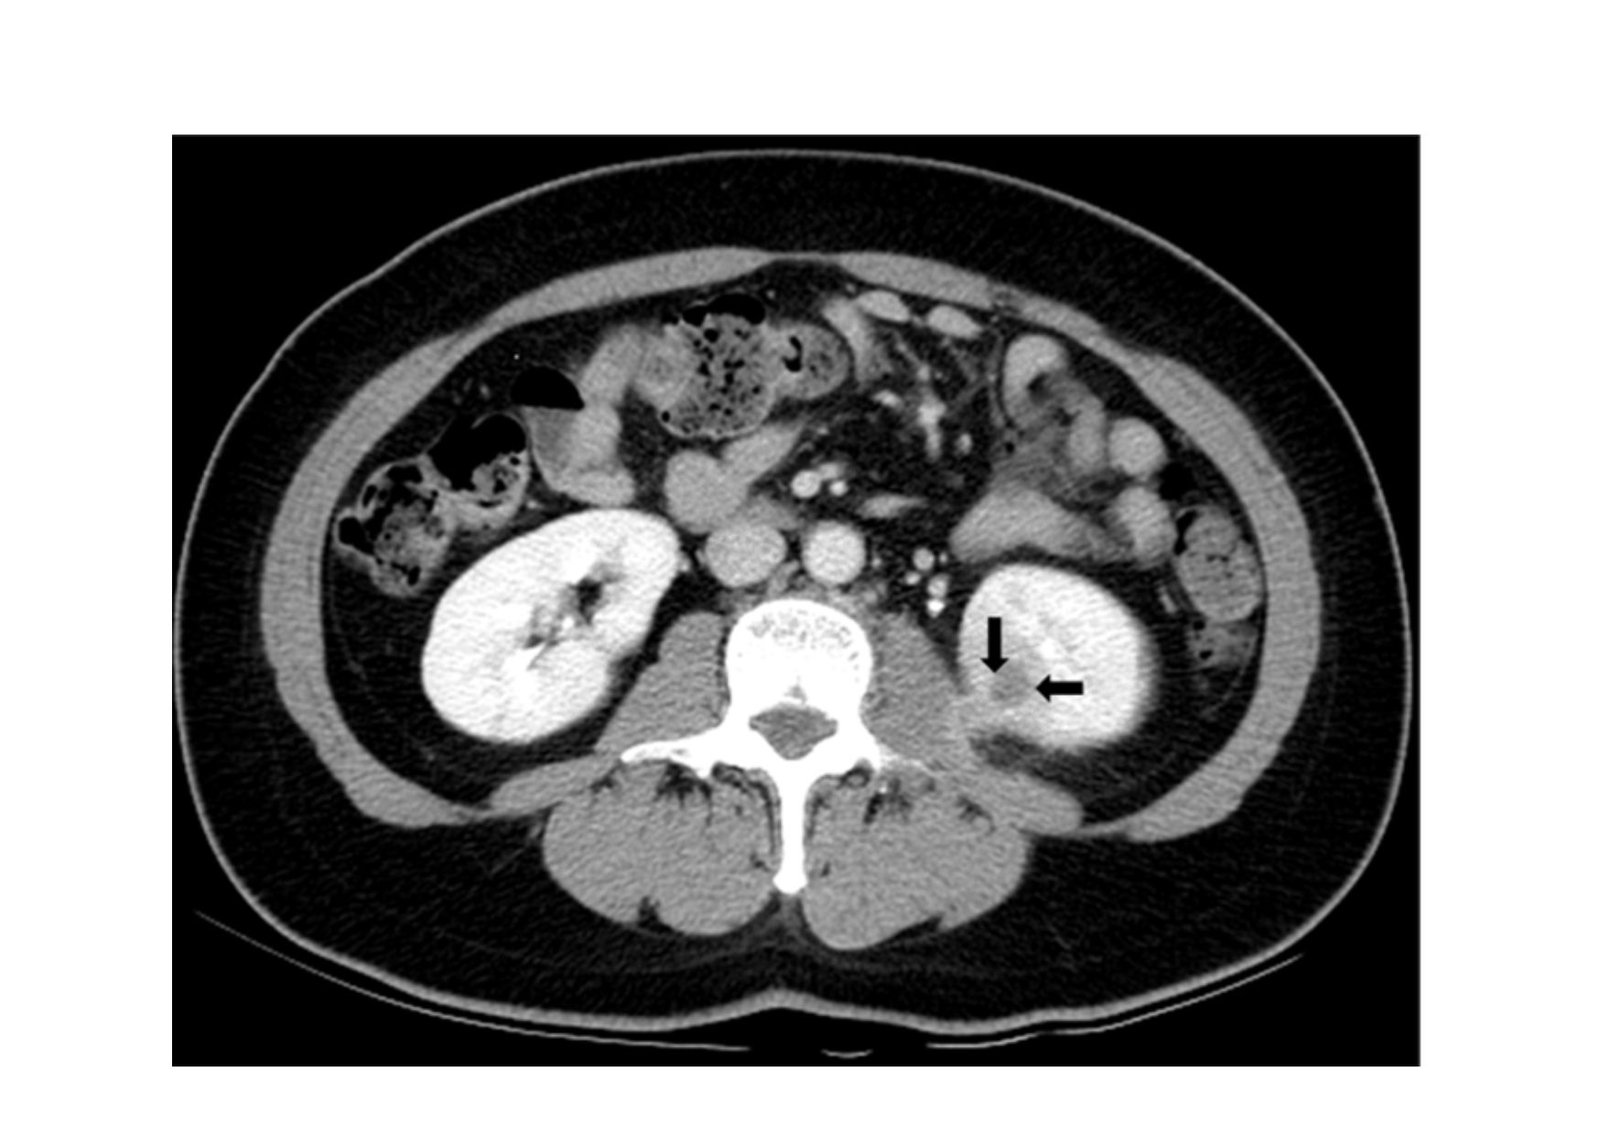

Image: Ultrasound in Diagnosing Urinary Tract Infections

Documenting these precise urinary tract infection ultrasound findings provides the referring physician with definitive evidence regarding the infection’s physical severity and precise anatomical location.

During the evaluation, the radiologist cross references the real time visual data against a standardized list of recognized clinical pathologies. The presence of any of the following structural abnormalities immediately confirms a complicated diagnosis.

Acute Pyelonephritis | Global physical enlargement of the affected kidney, a loss of the normal visual distinction between the cortex and the medulla, and localized hypoechoic (dark) regions indicating severe tissue edema. | Confirms the bacterial infection has successfully ascended from the bladder and actively invaded the functional renal tissue. |

Obstructive Urolithiasis | A brightly echogenic, highly reflective focal mass that casts a distinct, dark acoustic shadow directly posterior to its location within the kidney, ureter, or bladder. | Identifies the exact mechanical obstruction that is trapping urine and acting as a secure biological reservoir for the infecting bacteria. |

Hydronephrosis | Abnormal, pronounced dilation of the renal pelvis and internal calyces, appearing on the monitor as an interconnected network of dark, fluid filled spaces. | Confirms that a downstream physical blockage is actively forcing infected urine backward into the delicate filtering structures of the kidney. |